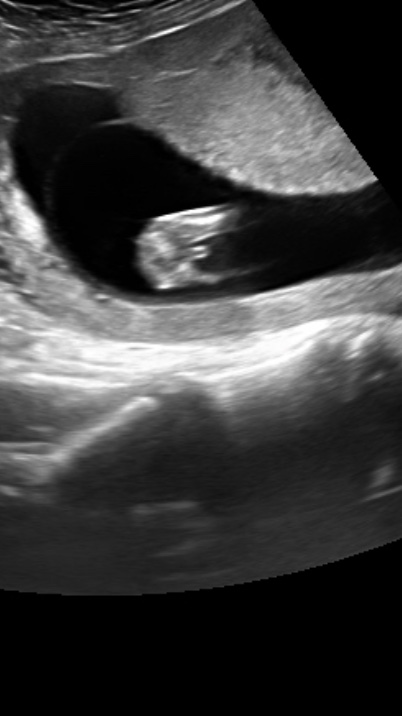

I’m driving myself mad looking for scan pictures similar to mine so I’m hoping somebody might have a guess for me on my scan pic and potty shot at 13 weeks! Baby was upside down so I’ve turned the pic around in hope it makes it easier to see!

Thanks so much! Attachment 39299